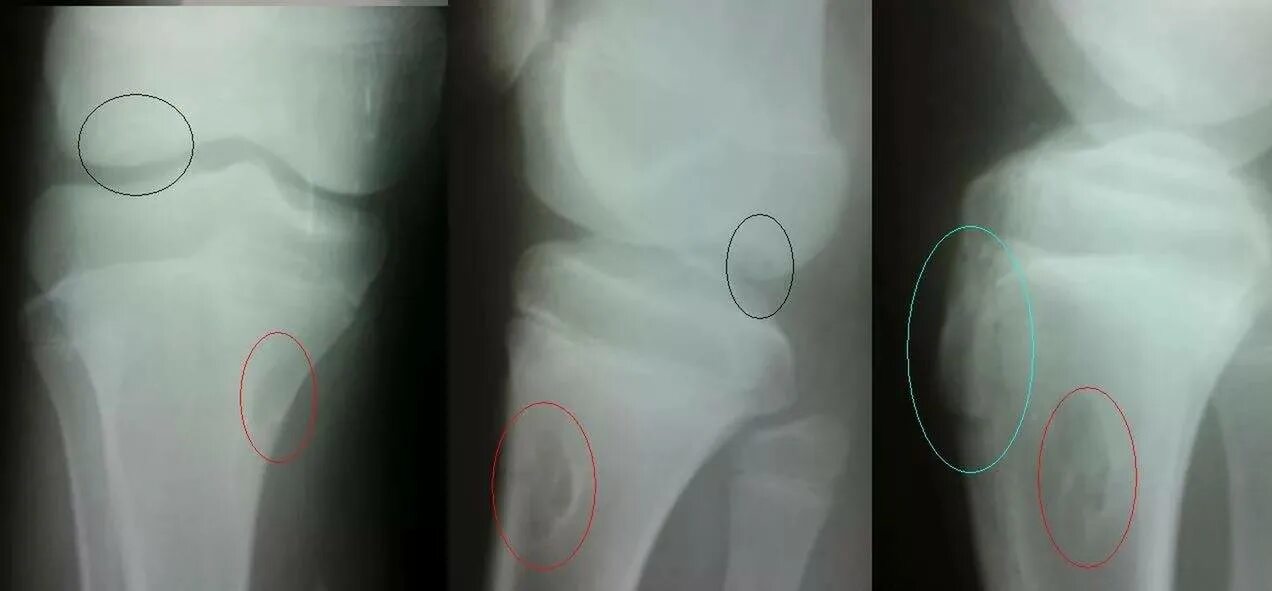

Синдром осгуда шляттера